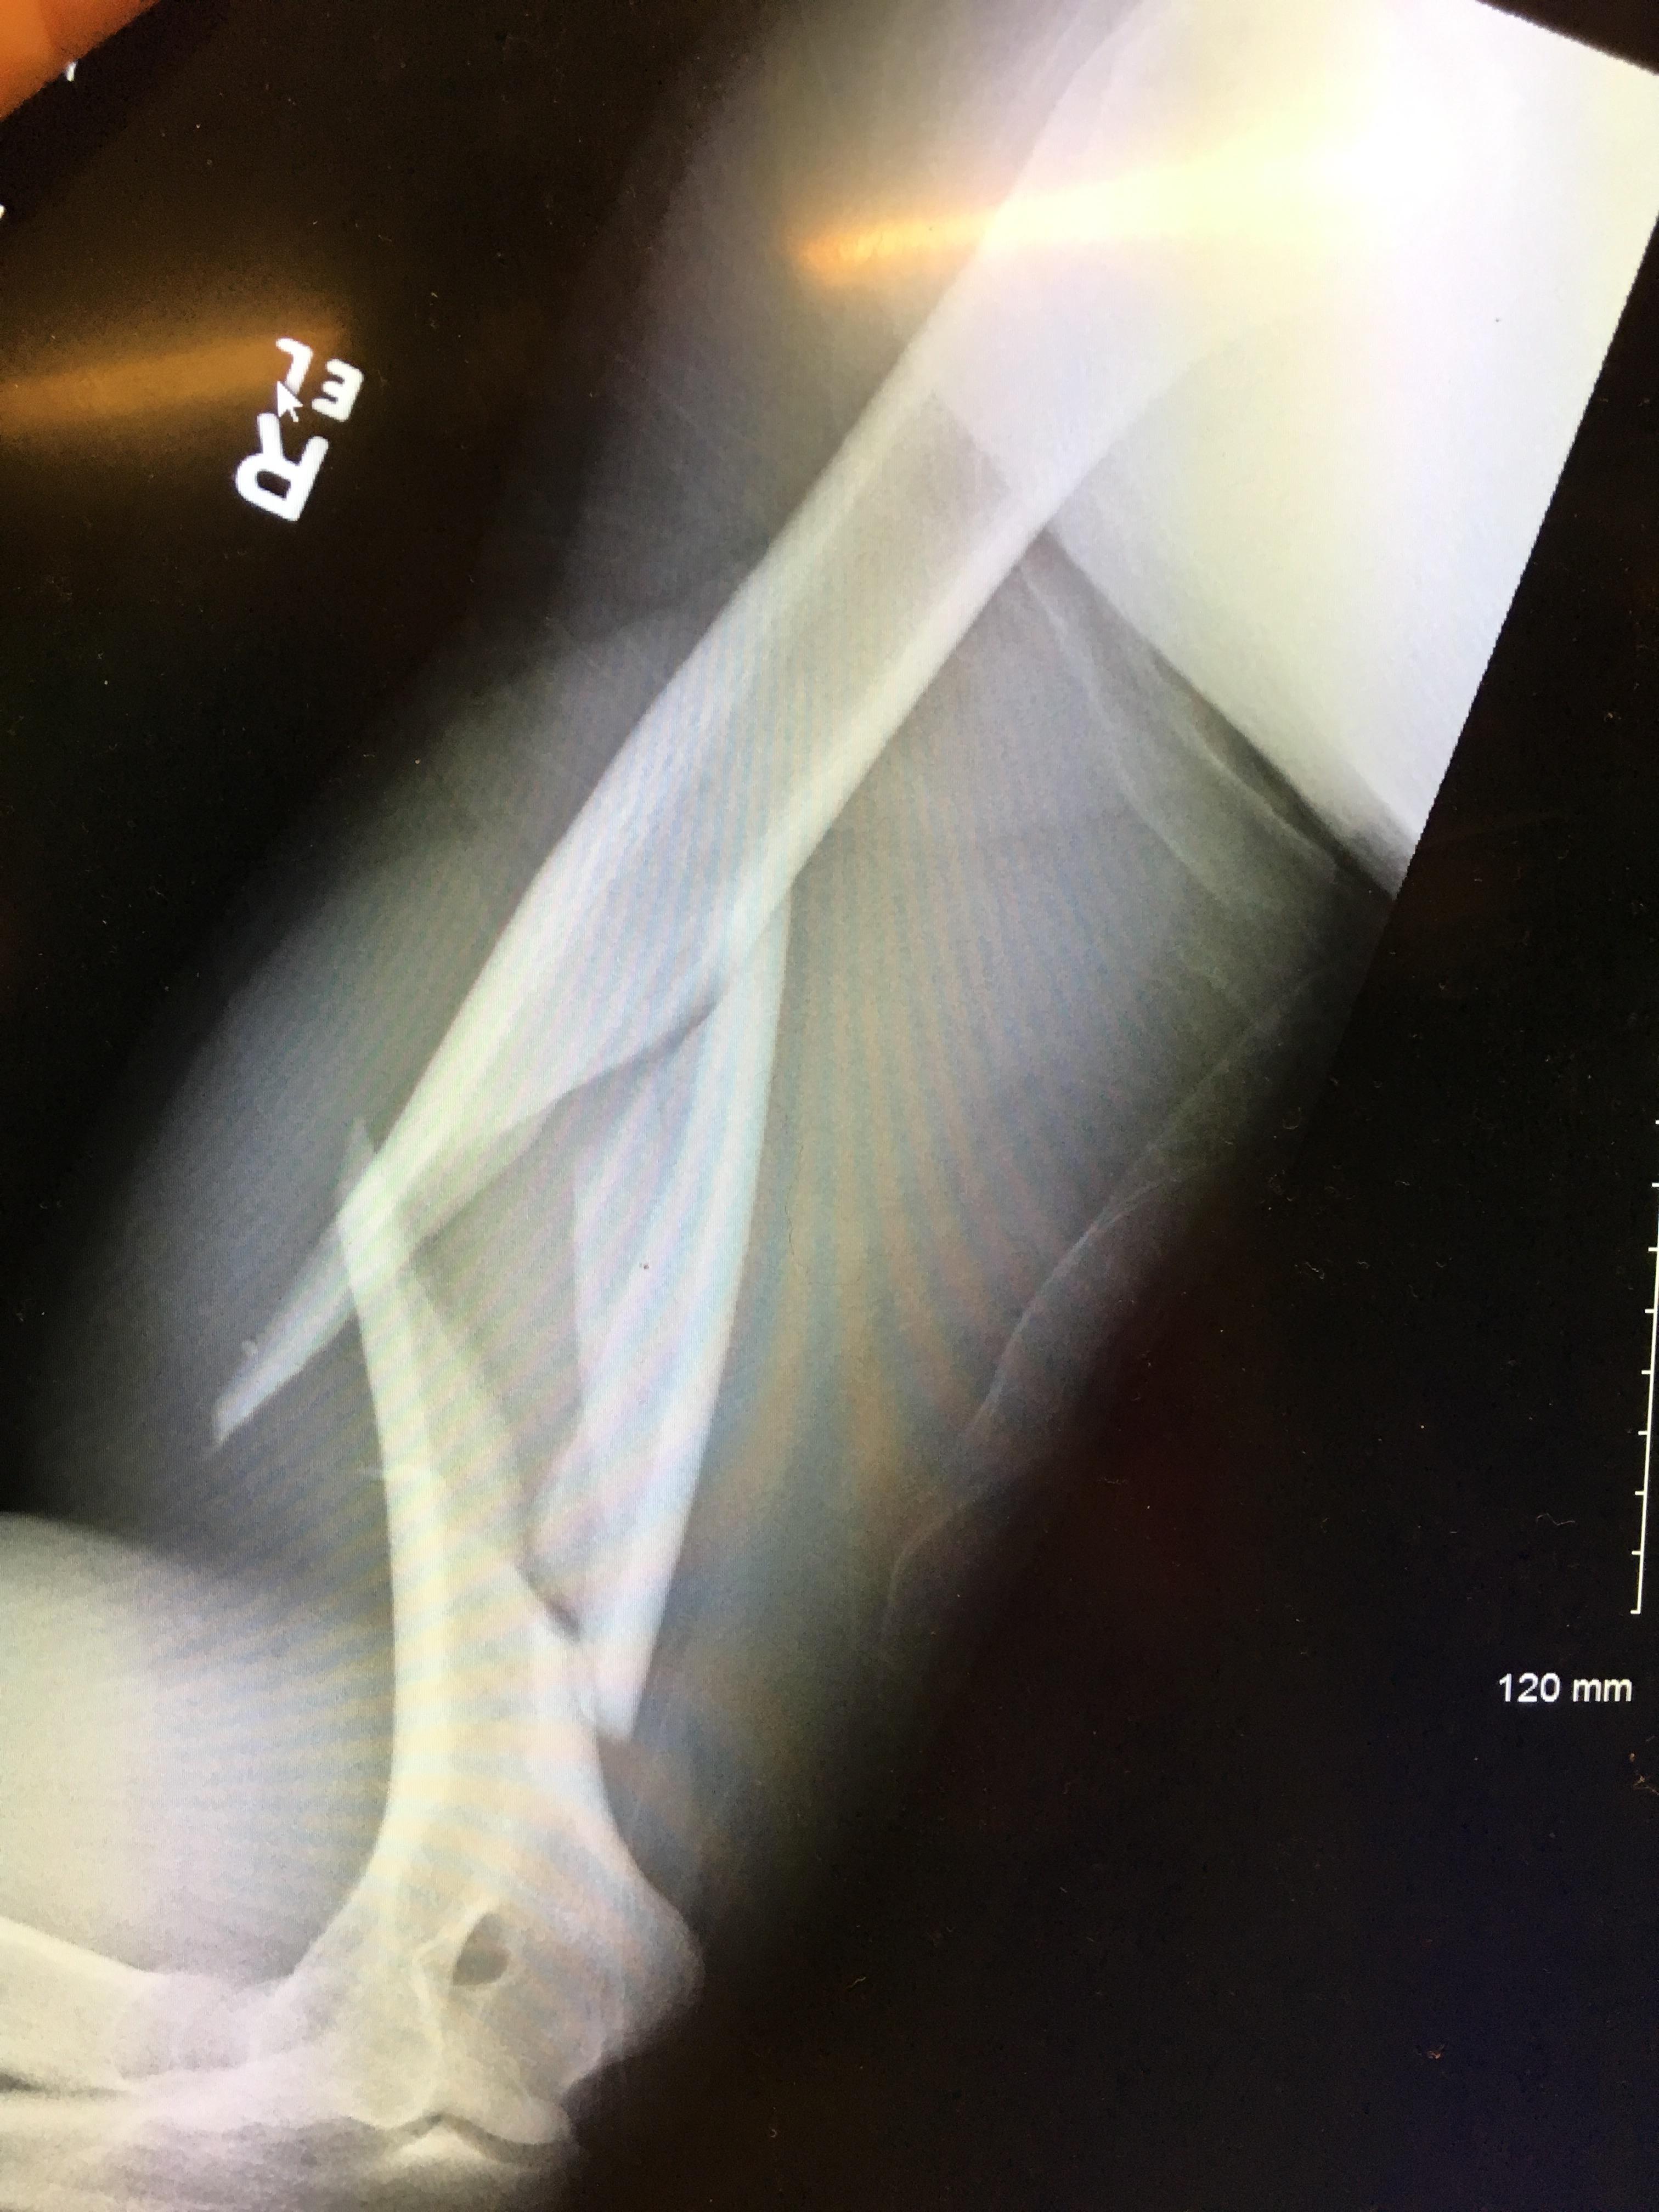

Figure 1 from Recurrent Throwing Fracture of the Humerus in a Baseball Baseball Fracture The mechanism of hook of hamate fractures in baseball players is predictable, most often developing secondary to repetitive swinging. It can also affect grip strength and. Meticulous adherence to the described surgical technique tailored to athletes optimizes clinical outcomes and avoids complications. Distal radius fracture is a fracture of the distal metaphysis of the radius with or without articular involvement.. Baseball Fracture.

Worst Gruesome baseball injury Snapped humerus throwers fracture YouTube Baseball Fracture The mechanism of injury for hook of the hamate fractures in baseball players is most commonly due to compression while swinging a bat but may. Meticulous adherence to the described surgical technique tailored to athletes optimizes clinical outcomes and avoids complications. The injury results when an unyielding object (like a ball) strikes the tip of the digit and forces it. Baseball Fracture.